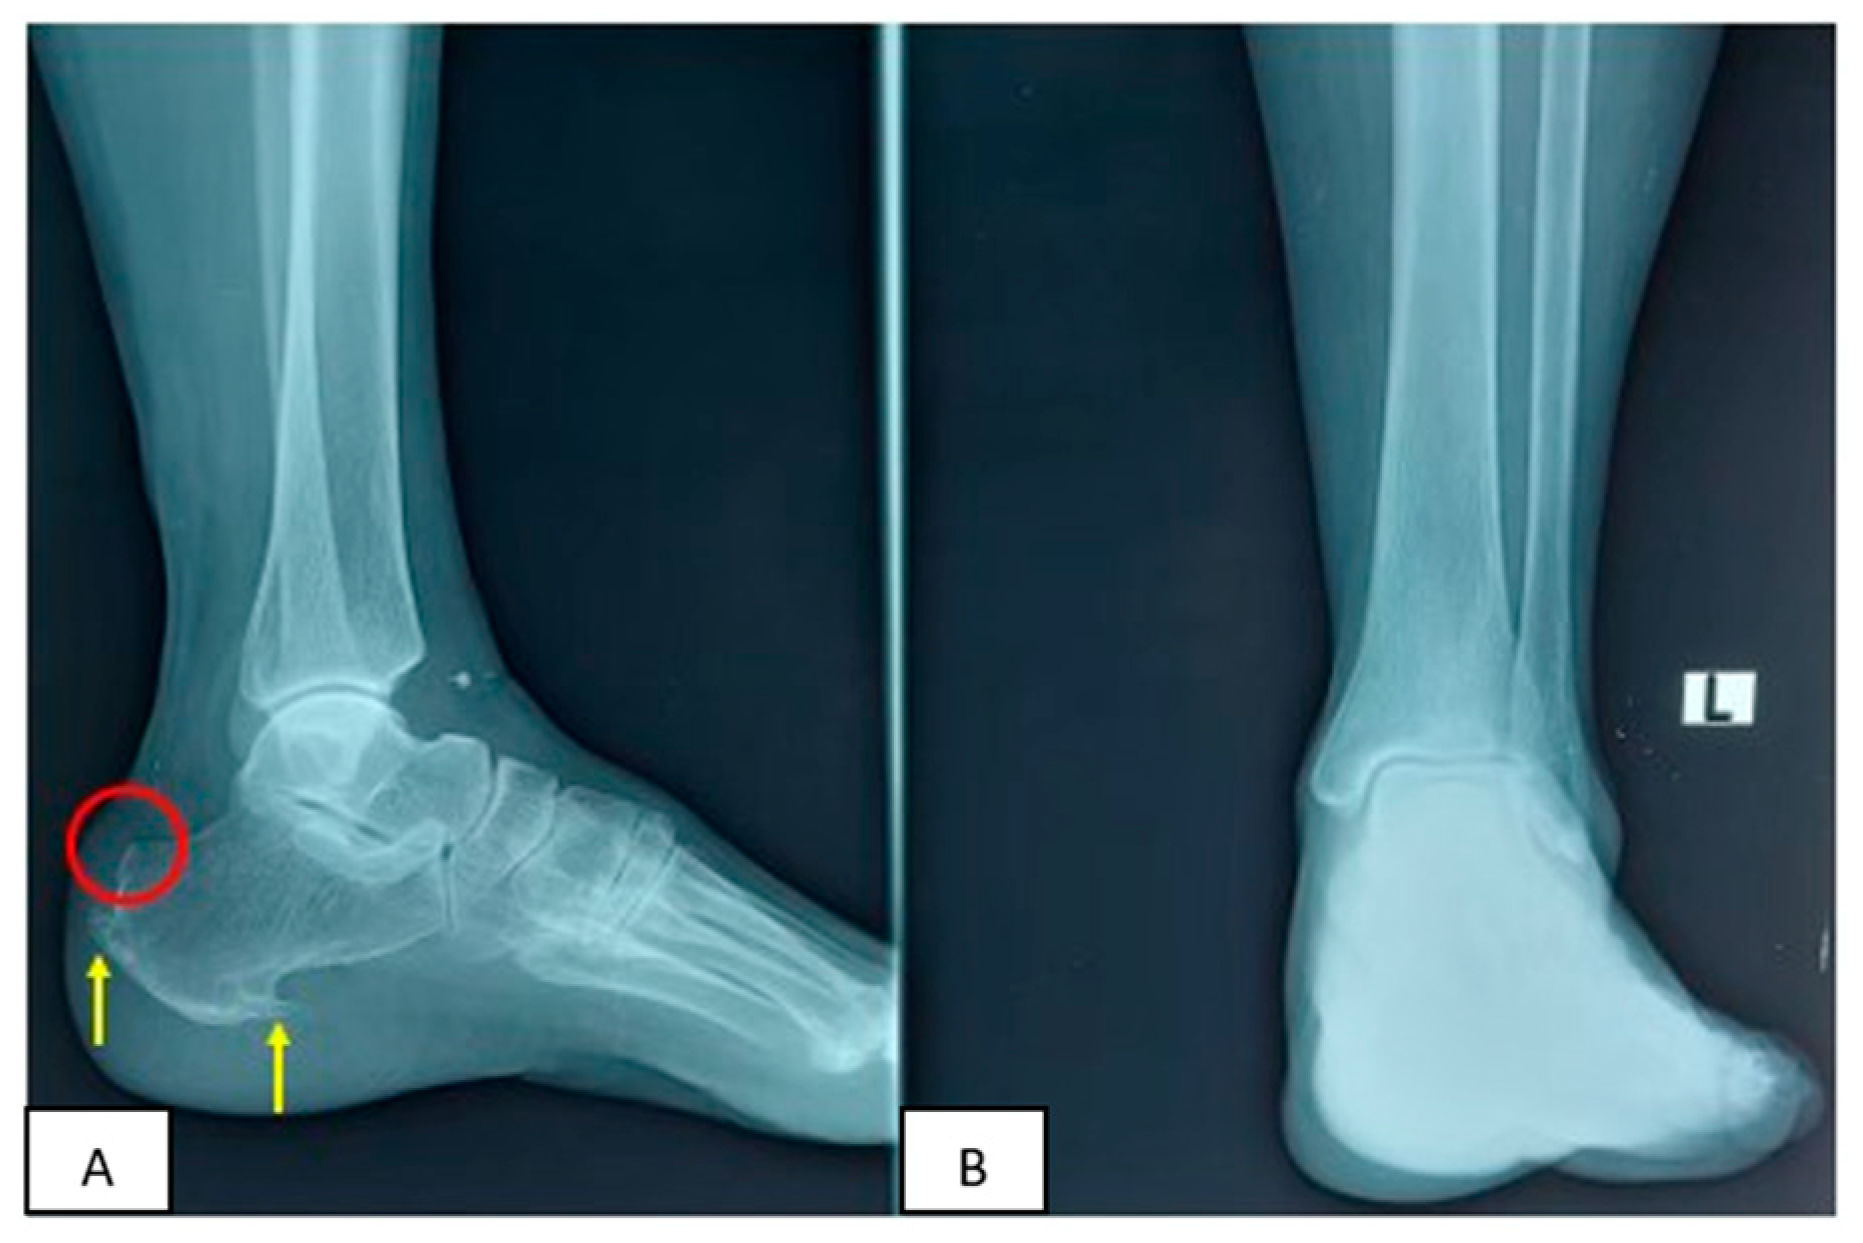

2. Clinical Case